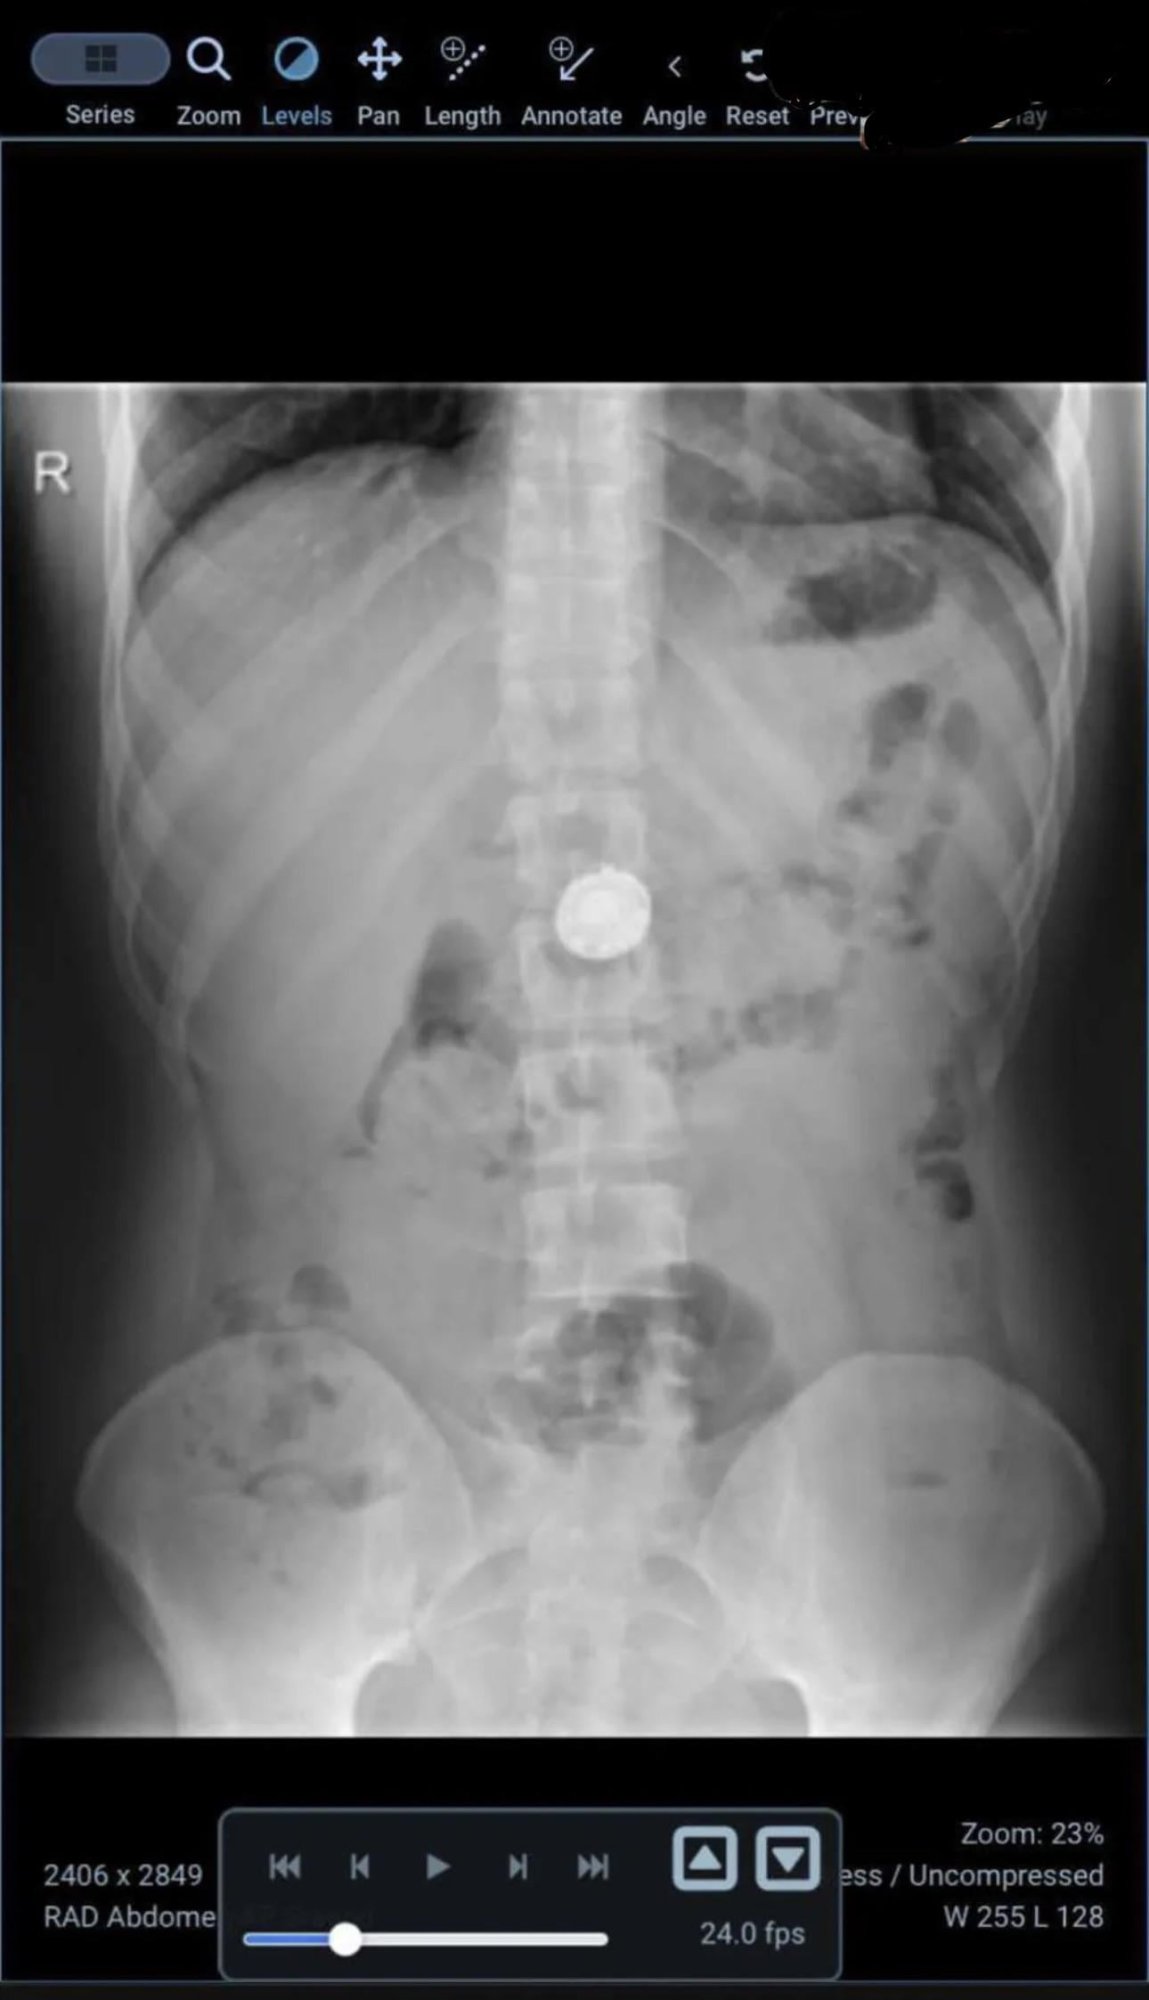

Why does the AirTag in the x-Ray look like it’s outside the rib cage?

It looks more like it’s on top of the dog.

If you look closely, the bones are quite transparent to the X-rays. The AirTag reflects so much more that it shines through the bones, outshining them.